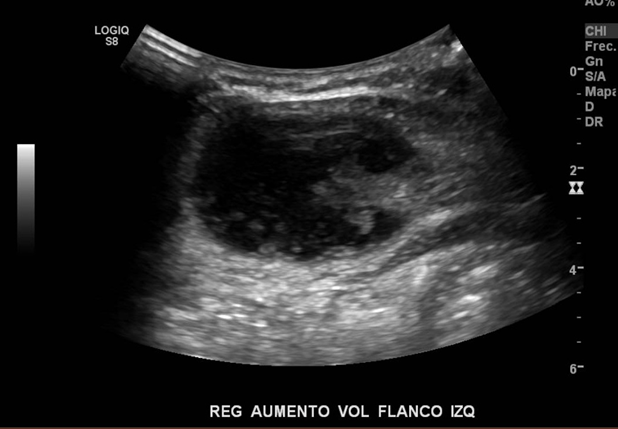

Se solicita ecografía abdominal sin diagnóstico a paciente masculino de 22 años, extranjero, que acude a centro médico por aumento de volumen en flanco izquierdo hace 1 semana, sin dolor ni cambios cutáneos, sin otros antecedentes asociados. No presenta antecedentes mórbidos ni cirugías previas.

Al evaluar región de aumento de volumen se puede observar imagen quística con leve señal al Doppler en región sólida, se sugiere exámenes complementarios.